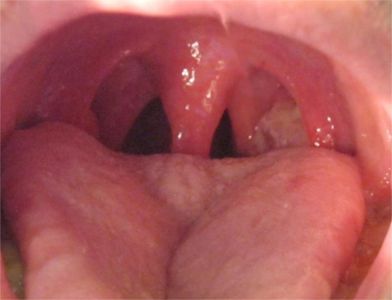

扁桃体癌属于扁桃体恶性肿瘤,为口咽部常见恶性肿瘤之一,病因可能与烟、酒等因素有关。本病可引起咽部不适、异物感、疼痛感、溃烂、出血等症状,临床常通过活检进行确诊,临床多采取手术切除治疗。

扁桃体癌通常先表现为咽部不适、异物感,随后咽痛加剧,可出现吞咽困难。同时,检查可见扁桃体肿大,表面溃烂,呈结节状隆起,易出血,可与周围组织粘连。